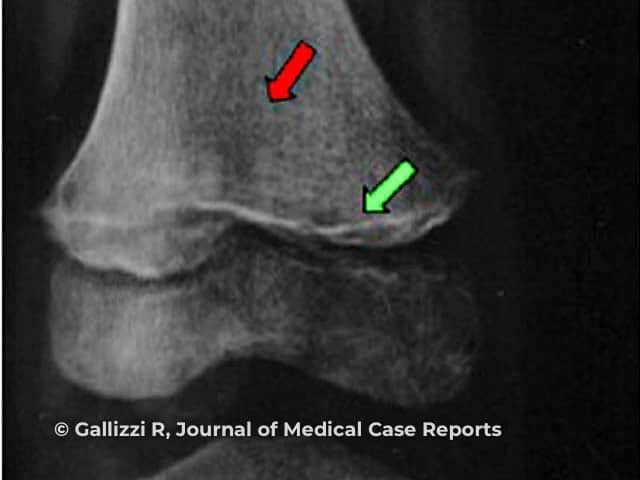

Frankel sign (green arrow), Trummerfeld zone (red arrow)

Image from: Gallizzi R, Valenzise M, Passanisi S, Pajno GB, De Luca F, Zirilli G. Scurvy may occur even in children with no underlying risk factors: a case report. J Med Case Rep. 2020;14(1):18.